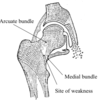

Describe the boney architecture of the head of the femur

In the head of the femur there are two main intersecting trabecular systems:

- SUPERIOR: medial bundle & arcuate bundle – formed due to the compression through head & neck

- INFERIOR: medial bundle & lateral bundle – formed in response to muscle pulls on greater & lesser trochanters

Where is the fracture risk in relation to the trabecular patterns?

Where the two main trabecular patterns intersect